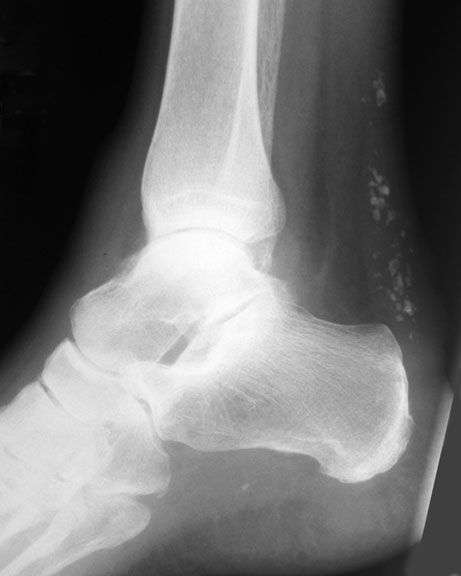

Calcification is a common inflammatory response. I would guess that inflammation is your mystery variable. For example, here's an x-ray showing calcification as a response to chronic tendinitis of the Achilles tendon.

• AchillesCaSmall-1.jpg

AchillesCaSmall-1.jpg

24.7 KB · Views: 936